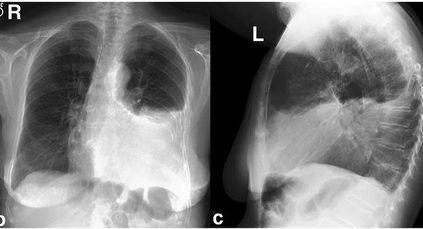

Among various medical imaging tools, chest radiographs are the most important and widely used diagnostic tool for detection of thoracic pathologies. Research is being carried out in order to propose robust automatic diagnostic tool for detection of pathologies from chest radiographs. Artificial Intelligence techniques especially deep learning methodologies have found to be giving promising results in automating the field of medicine. Lot of research has been done for automatic and fast detection of pneumothorax from chest radiographs while proposing several frameworks based on artificial intelligence and machine learning techniques. This study summarizes the existing literature for the automatic detection of pneumothorax from chest x-rays along with describing the available chest radiographs datasets. The comparative analysis of the literature is also provided in terms of goodness. Limitations of the existing literature along with the research gaps is also given for further investigation. The paper provides a brief overview of the present work for pneumothorax detection for helping the researchers in selection of optimal approach for future research.